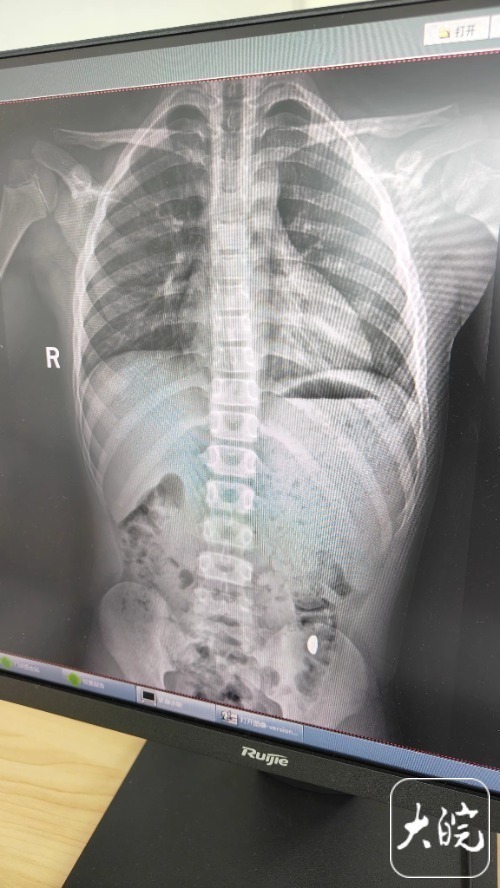

五天过去,纪女士扒了两次大便都没见金豆影子。10月26日一早,她拽着儿子往医院跑,门诊病历上“胃内异物”四个字让她手心直冒冷汗。结果刚做完腹部CT,儿子突然捂着肚子喊“要拉臭臭”,十分钟后举着马桶冲水口喊:“妈妈你看!闪闪发光的!”